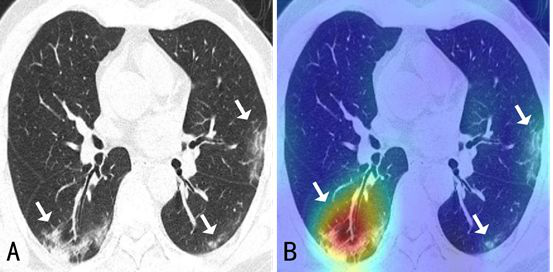

A: CT chest scan; B: Visual feedback from the AI system

The advantage of AI over the human eye, of course, lies in its efficiency. With Fudan’s AI system, lesions can be located within seconds while it takes a human radiologist 5-10 minutes.

Fudan’s AI diagnostic system is able to identify and classify types of diseases based on chest CT scans, telling COVID-19 from other viral or bacterial pneumonia. Compared to nucleic acid test, a widely used approach to diagnose infection, which returns a false-negative rate at 30%-50%, Fudan’s AI system reports such an occurrence as low as 7%.